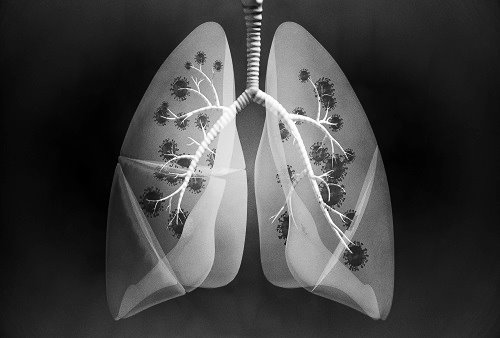

폐암 초기증상 세 번째는 호흡 곤란입니다. 폐암이 발생할 시에 초기증상으로 숨이 가쁜 증상을 느끼게 됩니다. 숨이 가쁜 증상의 하나인 만성 폐쇄성 질환인 COPD는 주로 흡연자에게 많이 나타나며, 기도 협착과 호흡기능 저하, 폐포 폐쇄 등의 증상이 발생하게 됩니다.

이럴 경우 숨이 가쁘고 호흡 능력이 나빠지면서 자가 호흡이 어려워져서 인공호흡기를 해야 하는 경우도 발생할 수 있기에 주의가 필요합니다. 폐암 초기증상이 나타나는 사람 2명 중 1명은 호흡곤란을 경험했다고 합니다. 이때 대부분의 증상이 있는 사람들이 대수롭지 않게 흡연이나 운동 부족으로 인한 단순 호흡곤란으로 생각하므로 조기 대처가 늦어지는 경우가 많습니다.

숨이 가쁜 증상의 하나인 만성 폐쇄성 질환인 COPD는 주로 흡연자에게 많이 발생하는데, 기도 협착과 호흡기능 저하 및 폐포 폐쇄 등의 증상이 나타납니다. 그리고 숨이 가쁘고 호흡기능이 떨어진다고 하면 자가 호흡이 어려워져 호흡기를 해야 하는 경우도 발생할 수 있기에 주의가 필요합니다.